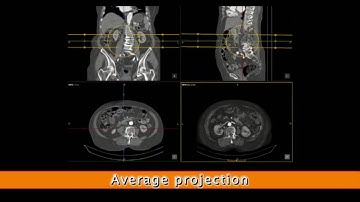

MPR-Reconstruction | PACScenter Tutorial